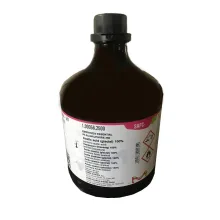

رنگ هماتوکسیلین کد 105175 500 میلی لیتر مرک

رنگ هماتوکسیلین کد 105175 500 میلی لیتر مرک

مشخصات محصول :

- محلول هماتوکسیلین

- C.I 75290 2g/l

- فرمول شیمیایی : C16H14O6

- فرمول تجاری Gill ll

- روش رنگ آمیزی پیش رونده

- متشکل از 34 g/l از Al2(SO4)3 18H2O

- دارای خاصیت اسیدی

- PH: 2.5-2.6

Hematoxylin 500ml Merck